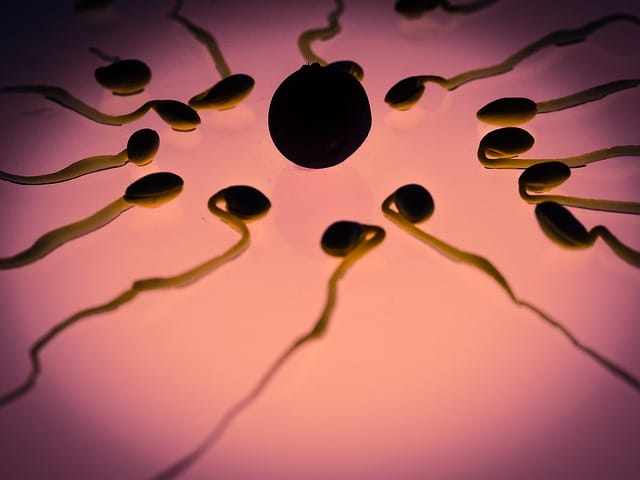

Σε εκδήλωση για τα 6 χρόνια επιτυχούς λειτουργίας γνωστού κέντρου υποβοηθούμενης γονιμοποίησης παρευρέθησαν εκπρόσωποι της Ελληνικής Κυβέρνησης και μίλησαν σχετικά με το δημογραφικό ζήτημα. Το θέμα αποτελεί προτεραιότητα, καθώς όπως φαίνεται και από τα στατιστικά δεδομένα ο ελληνικός πληθυσμός φθίνει. Πρόκειται για ένα γεγονός που υφίσταται σε παγκόσμια κλίμακα. Η υποβοηθούμενη γονιμοποίηση αποτελεί βασικό πυλώνα αντιμετώπισης αυτού του φαινομένου. Ωστόσο, εγείρονται προβλήματα όπως το κόστος, η χρηματοδότηση και οι σύγχρονες δομές. Όλα αυτά τα προβλήματα καλείται η Ελλάδα να τα διαχειριστεί με τον καλύτερο τρόπο, παρέχοντας διέξοδο σε όσα ζευγάρια επιθυμούν να τεκνοποιήσουν.